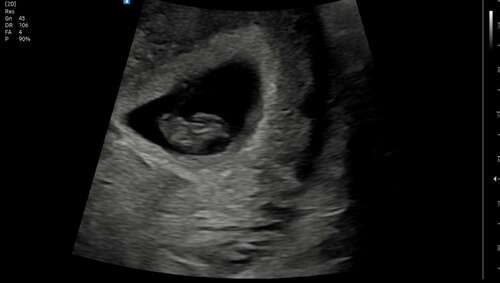

Hier de echo van 7+5 van het zijaanzicht via inwendige echo. Ik kan er niet veel van maken nog 😂😂